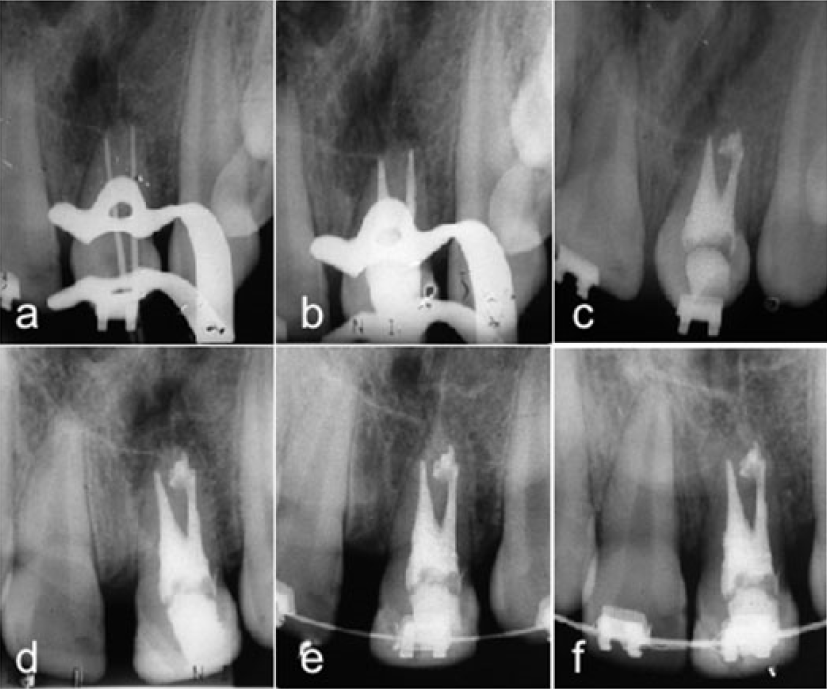

Obtido o comprimento real de trabalho foi confeccionado o batente apical com limas tipo K 35 e escalonamento regressivo com limas tipo K 40, 45, 50 e 55 alternando a lima tipo K 35 entre o uso da cada uma das limas do escalonamento. Foi realizada irrigação final com hipoclorito de sódio (NaOCl) a 2,5 % com uma ponta de ultrassom acionada com o aparelho ENAC (Osada Eletric Co, Ltd, Tokyo Japan), os canais foram aspirados com cânula de sucção e novamente inundados com solução de E.D.T.A. trissódico 17 % (Biodinamica, Ibiporã, Brasil) agitada com a mesma ponta de ultrassom por um minuto. Os canais radiculares foram lavados com solução salina estéril, aspirados e secos com pontas de papel absorvente estéril tamanho 40 Tanari (Tanariman industrial Ltda. Manacapuru, Brasil); colocação da medicação intracanal com hidróxido de Cálcio (Calen PMCC, S.S White Artigos Dentários Ltda. Rio de Janiero, Brasil) (Fig. 1, e) e restauração provisória com ionômero de vidro Maxxion R (FGM Produtos Odontológicos, Joinville, Brasil). Foram realizadas 3 trocas da medicação a cada 2 meses; frente a ausência de sinais e sintomas os canais radiculares foram obturados com cones de guta-percha de diâmetro 40 com conicidade 0.04 Tanari (Tanariman industrial Ltda. Manacapuru, Brasil), os quais foram colocados nos canais respeitando os comprimentos de trabalho de cada um e confirmados mediante a tomada de uma radiografia periapical (Fig. 2, a). Os canais foram preenchidos com o cimento AHPlus (Dentsply DeTrey GmbH, Konstanz, Alemanha) com auxílio da lima K 30 (Dentsply-Maillefer, Ballaigues, Suíça) abriu-se espaço para a colocação dos cones secundários, realizou-se a radiografia comprobatória para confirmar o correto preenchimento do material obturador (Fig. 2, b). Os cones foram cortados utilizando calcador Paiva (Golgran, São Caetano do Sul, Brasil) aquecido e em seguida realizou-se a limpeza da câmara pulpar com bolinhas de algodão embebido em álcool absoluto, sendo o elemento dentário selado provisoriamente com cimento de ionômero de vidro Maxxion R (FGM Produtos Odontológicos, Joinville, Brasil) cor A3 Universal. Foi realizada a radiografia periapical final do tratamento, onde contatou-se imagem radiopaca no periápice da raiz distal relacionado ao extravasamento de cimento endodôntico (Fig. 2, c). A paciente foi submetida ao tratamento ortodôntico para alinhamento e nivelamento dos dentes e encaminhada para a execução da reabilitação definitiva do elemento dentário. Exames clínicos e radiográficos de controle foram realizados a cada 6 meses no primeiro ano e depois, anualmente (Fig. 2, d, e, f) até o presente.

a) Radiografia da prova de cones. b) Comprovação da obturação. c) Radiografia final da obturação. d) Radiografia controle 1 ano. e) Radiografia controle 2 anos.